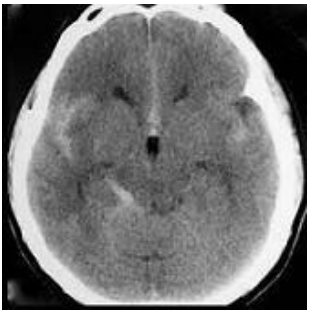

Homem, 33 anos, atleta, apresentando mal estar após cefaléia súbita intensa (escore 8/10) durante prática de salto com vara. Foi trazido ao pronto socorro por sua equipe, já recuperado do mal estar, porém com desorientação temporo-espacial e leve rigidez de nuca. Negavam trauma cranioencefálico. Os exames laboratoriais não demonstraram nenhuma alteração. Submetido a tomografia de crânio que demonstra hemorragia subaracnóidea (HSA) (figura 2).

Figura 2 Tomografia de crânio

Diante do exposto, assinale a alternativa que apresenta a classificação clínica e radiológica desse paciente.